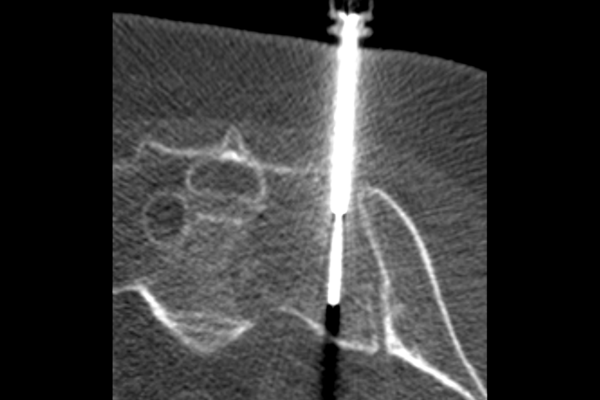

Our program trains all aspects of musculoskeletal radiology, including sports medicine, trauma, arthritis, rheumatology, tumors, and infectious disease. We also offer robust procedural training with ultrasound, spine injection, vertebroplasty, biopsy and ablation. Fellow education is enhanced by numerous interdisciplinary conferences, including arthroscopy correlation, orthopedic oncology, rheumatology, sports medicine and instructive case presentations.

The Musculoskeletal Imaging and Intervention Section at the University of Wisconsin provides imaging interpretation and imaging-guided intervention of the spine and extremities.

The section is composed of internationally renowned experts in all modalities used to image the spine and joints, and skilled professionals in injections to treat back and neck pain. The Musculoskeletal Imaging and Intervention Section also provides rapid, expert confidential consultation of spine, joint and extremity imaging and interventional cases, including complex sports medicine imaging.

Procedures

14.2K

MR Exams

5.2K

CT Exams

5.4K

Ultrasound Exams

2.1K

Spine Procedures